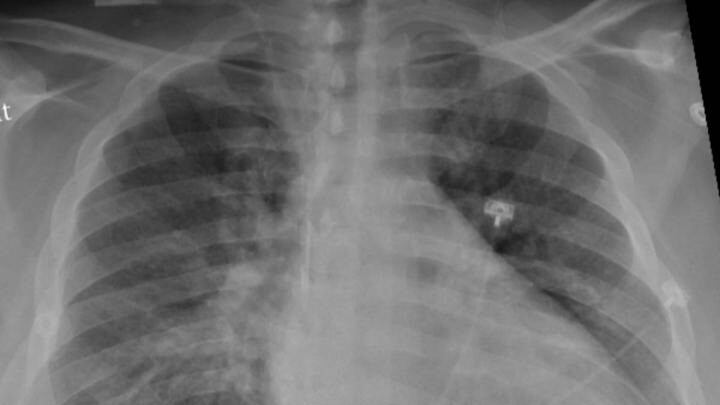

Las infecciones por covid-19 pueden provocar graves inflamaciones del pulmón y la formación de tejido cicatricial (fibrosis). Esto puede repercutir a largo plazo en la función pulmonar y es una de las causas del covid persistente.

En los pacientes de covid, unas células inmunitarias llamadas macrófagos desempeñan un papel importante en las infecciones inflamatorias graves y los daños pulmonares. Sin embargo, cuando el nuevo fármaco bloqueó la molécula de microARN de los macrófagos en ratones, se produjo una reducción significativa de la inflamación y el daño pulmonar y una mejora considerable de la función pulmonar.